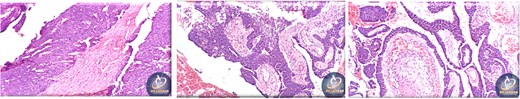

A 42-year-old male previously diagnosed with maxillary nasal sinus squamous cell carcinoma (SCC) was hospitalized for surgical treatment of recurrent infiltrating AC. The patient experienced three recurrences with the initial treatment approach for the cancer as SCC, a non-keratinizing variant. Complete excision and curettage of the lining mucosa were performed. In the second recurrence, the patient underwent additional curettage and subsequently revealed the absence of tumor residues from the mucosa and submucosa. However, the patient experienced a third recurrence with rapid growth and infiltration to the floor of the right maxillary sinus, filling the sinus space, infratemporal fossa, pterygopalatine fossa, cheek buccal area, and orbital floor. The imaging studies were preformed revealing a neoplastic lesion centered on the right maxillary sinus measuring 10 × 5 × 4.5 cm with a low T1 signal, heterogeneous iso T2/STIR signal, and intense heterogeneous post-contrast enhancement (Fig. 1). AC was recognized as stage II based on Yang’s et al. classification system [6]. Right Subtotal maxillectomy was performed through a Weber Ferguson incision with a Dieffenbach extension, and the infiltration areas were cleared. The excised tumor mass from the right maxillary sinus with labeled surgical margins (palate, orbital floor, buccal, and pterygoid surgical margins) was subjected to permanent paraffin evaluation (Fig. 2). The Right hemi-maxillectomy measuring 6 × 4.5 × 4 cm, revealed one canine, two molars, and two premolars found in the alveolar arch. An indefinite, grayish-white, infiltrating, fungating mass, approximately (⁓6 × 4 × 2.5 cm), was observed in the maxillary sinus. The cut surface of the mass was grayish-white and firm, with skeletal muscle attachment and noticeable infiltration into the underlying periosteum of the alveolar arch. Furthermore, labeled tumor tissue fragments measuring 4.7 × 2 × 2.5 cm and multiple smaller pieces collectively measuring 4 × 4 × 2 cm, showing similar characteristics, were stored in the same container. Microscopic examinations were performed at different magnifications. At a low magnification, the specimen revealed the presence of an infiltrative tumor with a biphasic pattern. The Islands and epithelial cell sheets are embedded in the fibrous stroma. The tumor islands exhibited a basaloid appearance with peripheral palisading, reverse polarity, and central stellate reticulum-like cells, reminiscent of ameloblastoma. However, these neoplastic epithelial cells exhibited moderate cytological atypia and increased mitotic activity, which suggests of malignancy (Fig. 3). Higher magnification shows tumor cells with enlarged, pleomorphic nuclei, prominent nucleoli, and eosinophilic cytoplasm. Frequent mitotic figures, including atypical forms, were also observed. Peripherally, tumor islands comprise cells with hyperchromatic elongated nuclei exhibiting focal palisading. The central cells were loosely cohesive and exhibited a stellate reticulum-like morphology. Additionally, focal areas of necrosis, hemorrhage, and keratinization were prominent in the tumor islands, and the surrounding stroma appeared desmoplastic and encompassed moderate chronic inflammatory infiltrates (Fig. 4). Additionally, diffuse infiltration of tumor into the adjacent tissues was observed, including bone and soft tissues, and is associated with perineural and lymphovascular invasion. Tumor extension in the orbital floor and buccal mucosal surgical margins was evident. In contrast, the palatal and pterygoid surgical margins are free of tumor involvement (Fig. 5). Overall, the morphological features were consistent with a diagnosis of infiltrating AC. Furthermore, immunohistochemistry assay was performed using a Ventana BenchMark GX Auto-stainer, employing the Ventana I View DAB detection system and Ventana monoclonal antibodies. The sections were stained for CK 5/6, P63, CK19, SOX-2, SOX-10, calretinin, and Ki67. The results revealed that the tumor basaloid epithelial component was strongly positive for P63 and showed weak heterogeneous positive staining for CK19, calretinin, and SOX-2 (Fig. 6). Conversely, it was negative for CK5/6 and SOX-10 staining. The Ki67 labeled index within the epithelial component was ⁓14%, whereas the mesenchymal component was 8%. The post-operative radiotherapy at 66 Gy was successfully administered. The patient is currently under observation, with careful follow-up.

Histopathological findings of specimen at higher magnification.